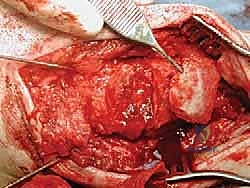

علاج هذه الكسور يتطلب مهارة فائقة من الدكتور محمد هطيف، حيث يتم استخدام تقنيات الجراحة الميكروسكوبية وتثبيت الكسور باستخدام صفائح معدنية دقيقة ومسامير (Locking Plates) دون المساس بثبات المفصل الصناعي، أو يتم دمج علاج الكسر ضمن عملية مراجعة المفصل الكلية إذا كان المفصل نفسه تالفاً.

الخطوة الثانية: النهج الجراحي (Surgical Approach)

يتم فتح الشق الجراحي الأمامي القديم بحذر شديد لتجنب إتلاف الأوعية الدموية والأعصاب، وهنا تبرز أهمية تقنيات الجراحة الميكروسكوبية التي يتقنها الدكتور هطيف.

الخطوة الثالثة: إزالة المفصل القديم (Explant Removal)

يتم استخراج المكونات المعدنية والبلاستيكية لمفصل (Agility) القديم بحرص بالغ للحفاظ على ما تبقى من العظم السليم.

الخطوة الرابعة: تنظيف العظم والترقيع (Debridement and Bone Grafting)

يتم تنظيف الأنسجة الملتهبة والأكياس العظمية. ونظراً لأن مفصل (Agility) يترك فراغاً كبيراً بعد إزالته، يتم استخدام طعوم عظمية (Autograft من حوض المريض أو Allograft من بنك العظام) لملء الفراغات وبناء أساس قوي.

الخطوة الخامسة: تركيب المفصل الجديد أو الدمج

يتم إدخال المفصل الجديد المخصص للمراجعة، والذي يحتوي غالباً على سيقان (Stems) تدخل عميقاً في عظمة الساق وعظمة الكاحل لضمان الثبات الميكانيكي. في حال وجود كسور في الكعب، يتم تثبيتها في هذه المرحلة.

الخطوة السادسة: الإغلاق التجميلي